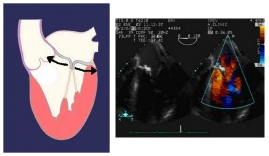

Insufficienza mitralica di tipo IIIb, dovuta a limitazione dei lembi valvolari durante la sistole.

Insufficienza mitralica di tipo II, dovuta a rottura o stiramento di una corda tendinea (a sinistra e al centro), o a rottura di un muscolo papillare (a destra).